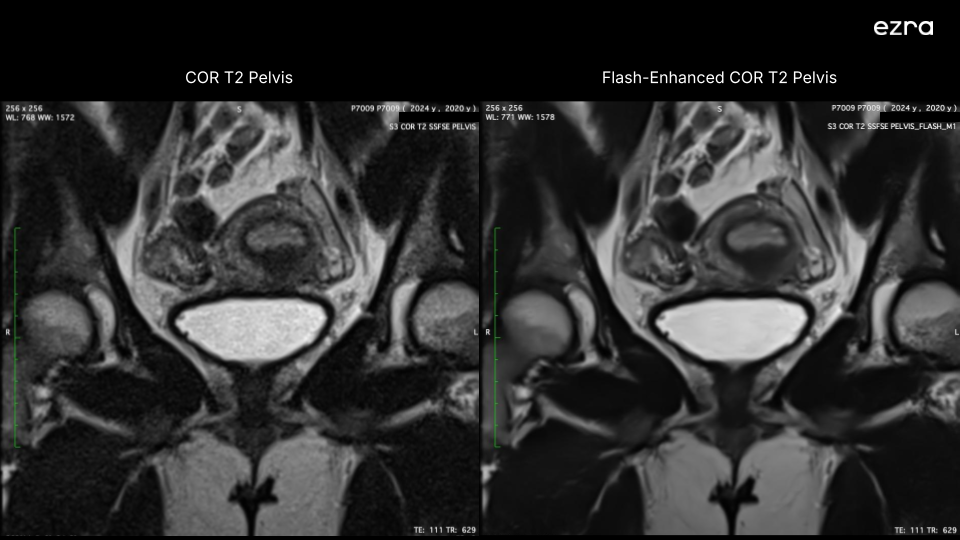

I'm excited to share that Ezra has received new FDA 510(k) clearance for a new version of our Ezra Flash AI. This clearance significantly expands our ability to enhance MR image quality, including the abdomen and pelvis, building upon our previous neuro imaging capabilities.

First, our Ezra Flash AI now delivers improved image quality by effectively reducing noise while preserving crucial diagnostic information across neuro, abdomen, and pelvis. This enhancement is particularly important for complex anatomical areas like the abdomen and pelvis, where clear imaging is essential for accurate screening.